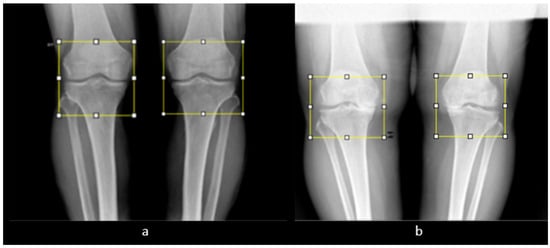

3.2. Preprocessing